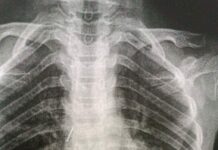

Ошто дарыгерлер канцелярдык мык жутуп алган баланы куткарышты

Ош облустар аралык балдар ооруканасынын дарыгерлери канцелярдык мык жутуп алган 10 жаштагы баланы куткарып калышты. Бул тууралуу аталган ооруканадан билдиришти.

Маалыматка караганда, канцелярдык мык жутуп...